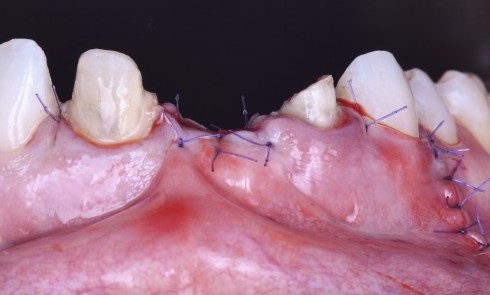

Article réservé à nos abonnés Relation ortho-parodontale. Réflexion autour d’un cas clinique

Parodontologie La parodontologie Hospitalo-Universitaire à l’École de médecine dentaire de Marseille est dirigée par le Pr Virginie Monnet-Corti. Elle s’appuie...